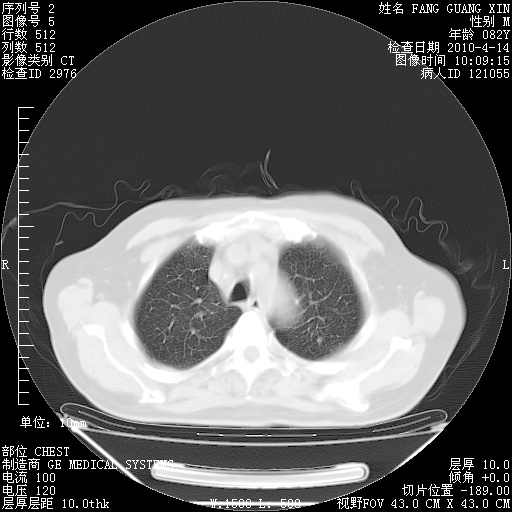

4月14日肺部CT

23.JPG

24.JPG

25.JPG

26.JPG

肺部CT平扫未见异常。